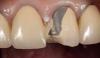

Пациентка 60 лет обратилась с просьбой эстетического восстановления скола керамики. В анамнезе скол произошел 2 года назад. Проводились неоднократно попытки реставрации скола классической техникой как при реставрации композитом, но они носили кратковременный успешный характер. На предложение произвести замену имеющегося протеза, отказалась. Запланировала это сделать позже. В данный момент, ее очень сильно интересовала возможность эстетического восстановления в полости рта. Этапы нашей работы.